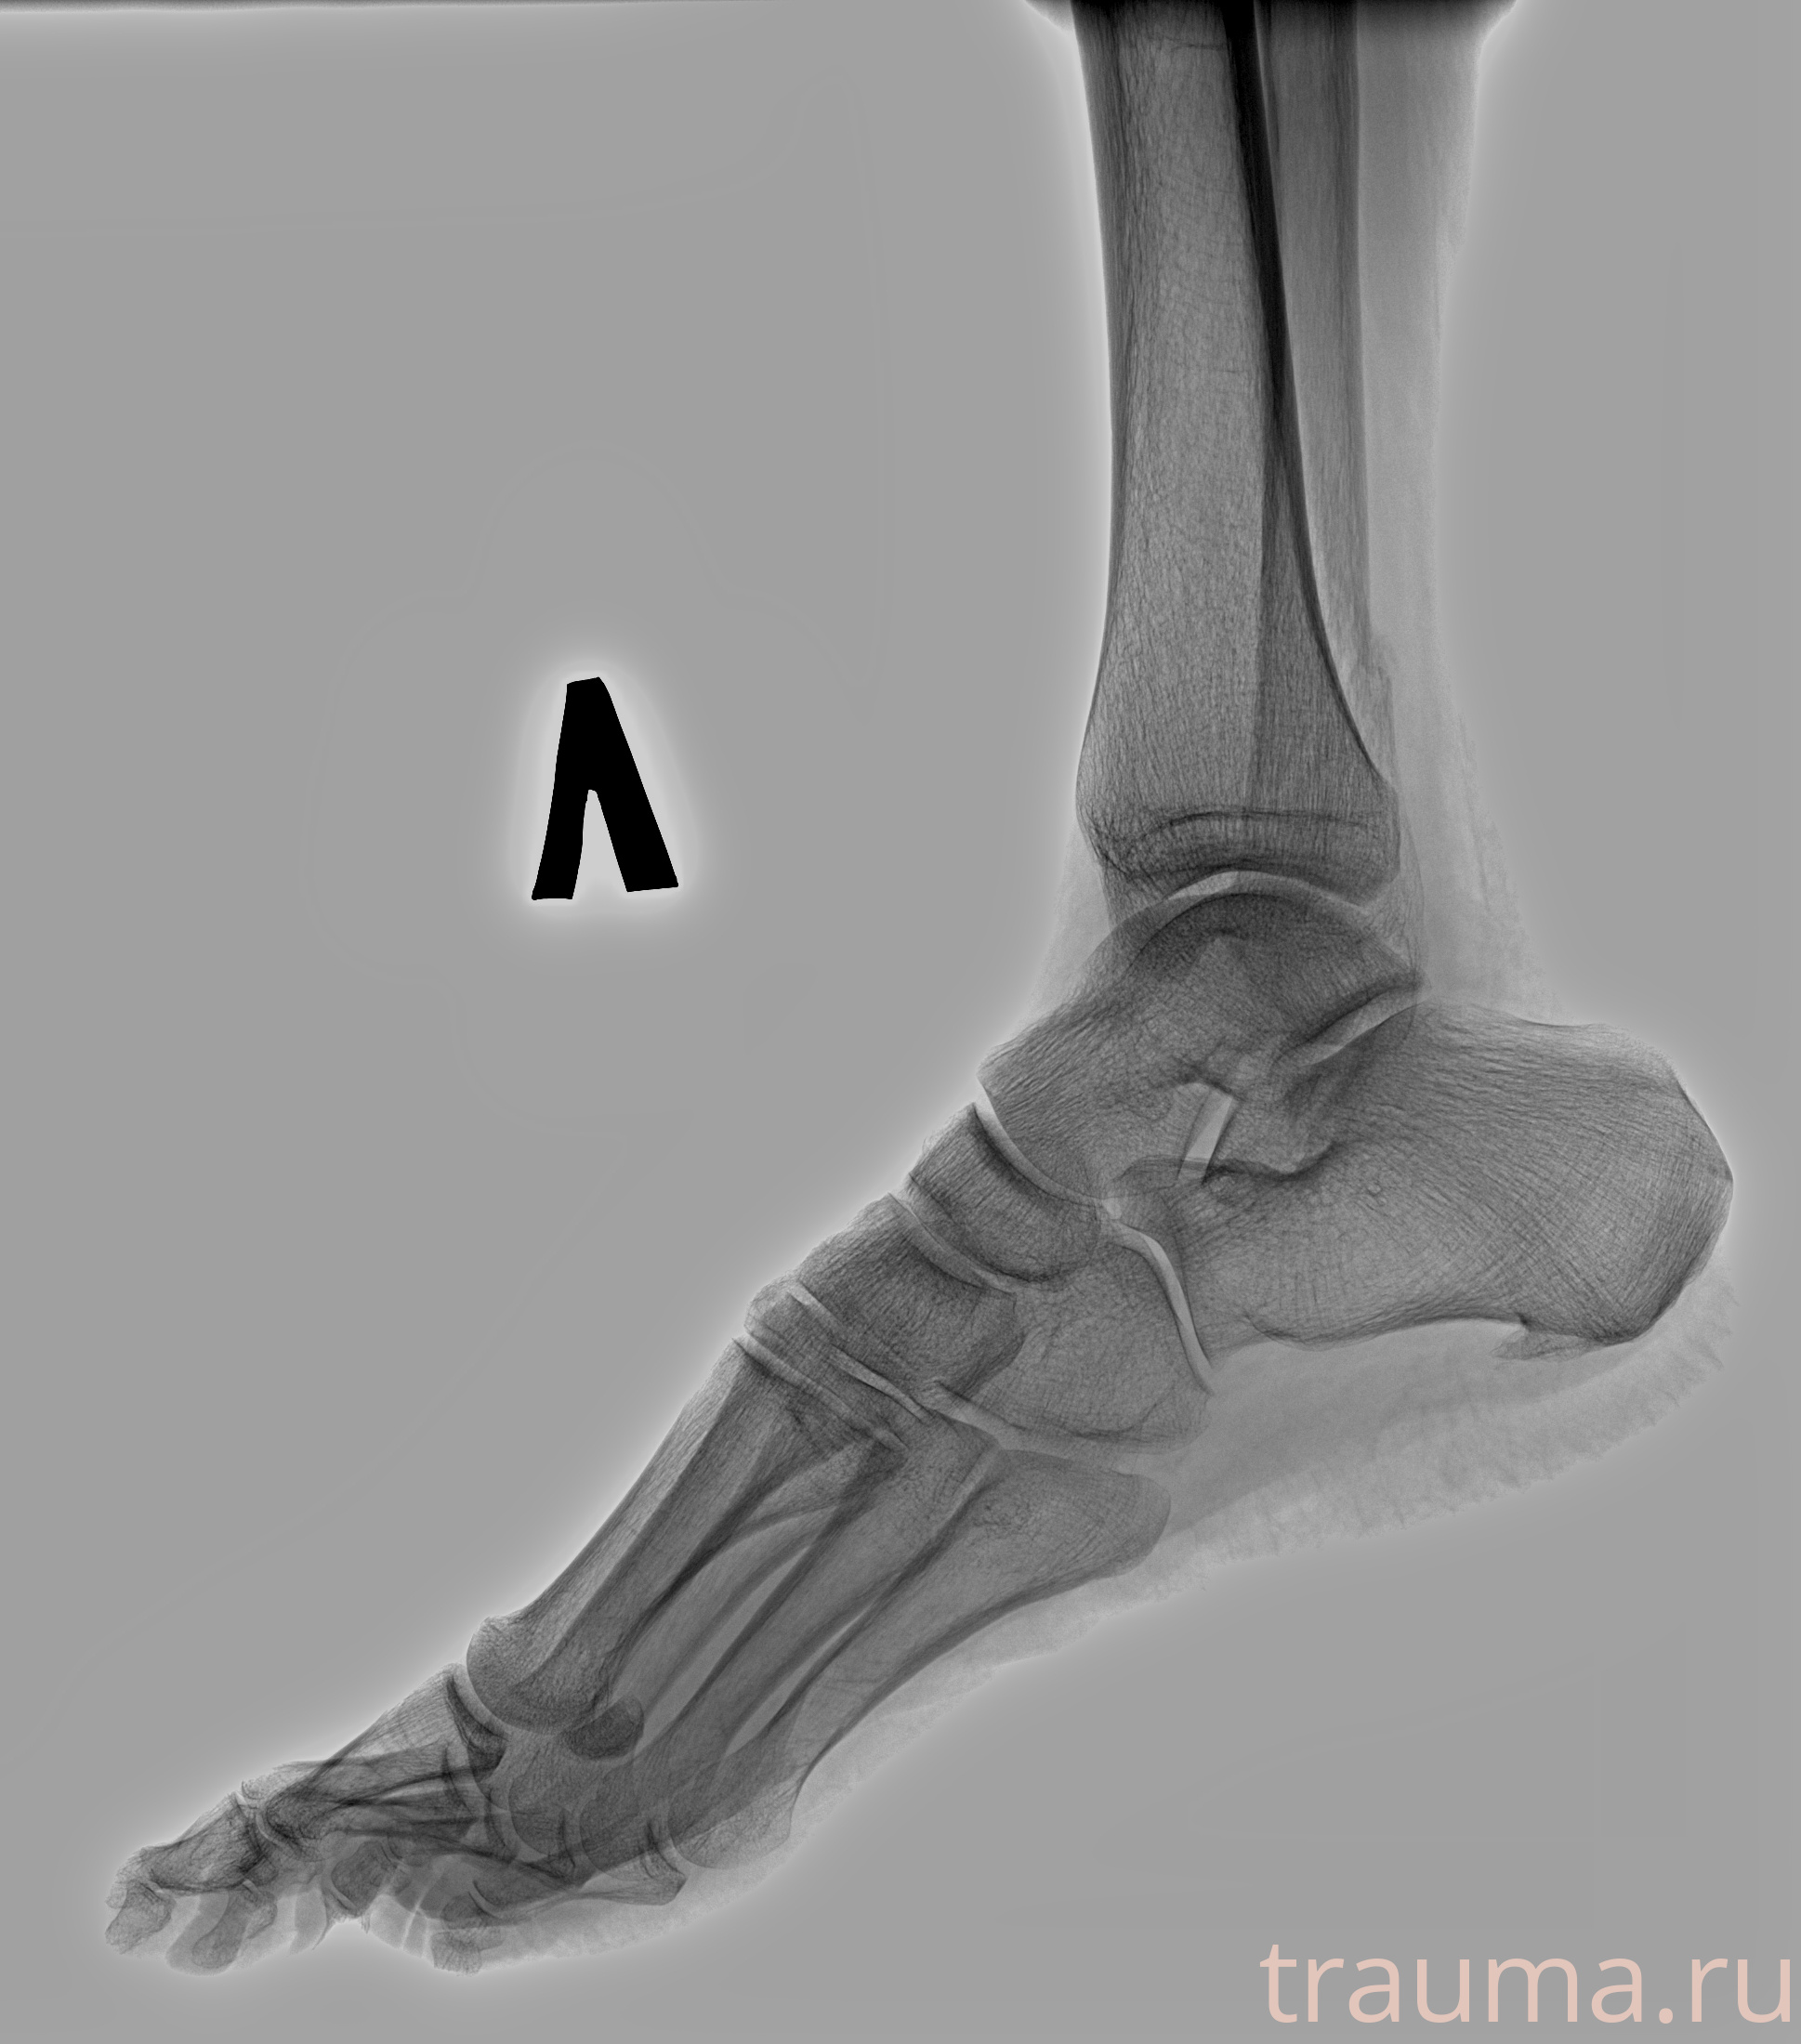

Рентгенограммы

Рентген на дому: по вашему адресу приезжает врач-рентгенолог, травматолог-ортопед с мобильным рентгеновским аппаратом, проводит диагностику травмы или заболевания, делает необходимые рентгенограммы, дает рекомендации по дальнейшему лечению. Получить качественные снимки в домашних условиях возможно благодаря уникальной методике, разработанной МосРентген Центром для института  Склифосовского